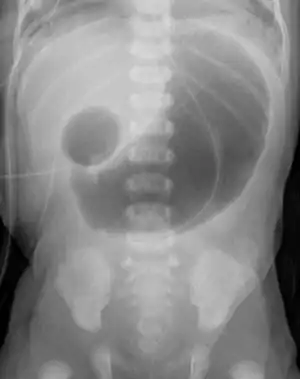

| Radiograph of abdomen with double-bubble sign from duodenal atresia | |

Duodenal atresia is the congenital absence or complete closure of a portion of the lumen of the duodenum. It causes increased levels of amniotic fluid during pregnancy (polyhydramnios) and intestinal obstruction in newborn babies. Newborns present with bilious or non-bilous vomiting (depending on where in the duodenum the obstruction is) within the first 24 to 48 hours after birth, typically after their first oral feeding. Radiography shows a distended stomach and distended duodenum, which are separated by the pyloric valve, a finding described as the double-bubble sign.

The diagnosis of duodenal atresia is usually confirmed by radiography. An X-ray of the abdomen is the first step in evaluation. The x-ray should be obtained after placement of a nasogastric tube (feeding tube), evacuating the stomach and filling 40-50 ml of air [6] to demonstrate two large air filled spaces, the so-called "double bubble" sign.[7][8] The air is trapped in the stomach and proximal duodenum, which are separated by the pyloric sphincter, creating the appearance of two bubbles visible on x-ray. Since the closure of the duodenum is complete in duodenal atresia, no air is seen in the distal duodenum. Note that the double bubble sign is typically pathologic however it is not specific for duodenal atresia and may indicate other pathologies such as annular pancreas or midgut volvulus.[9] A limited upper gastrointestinal series using barium contrast can be used to differentiate between duodenal atresia and midgut volvulus. [10]